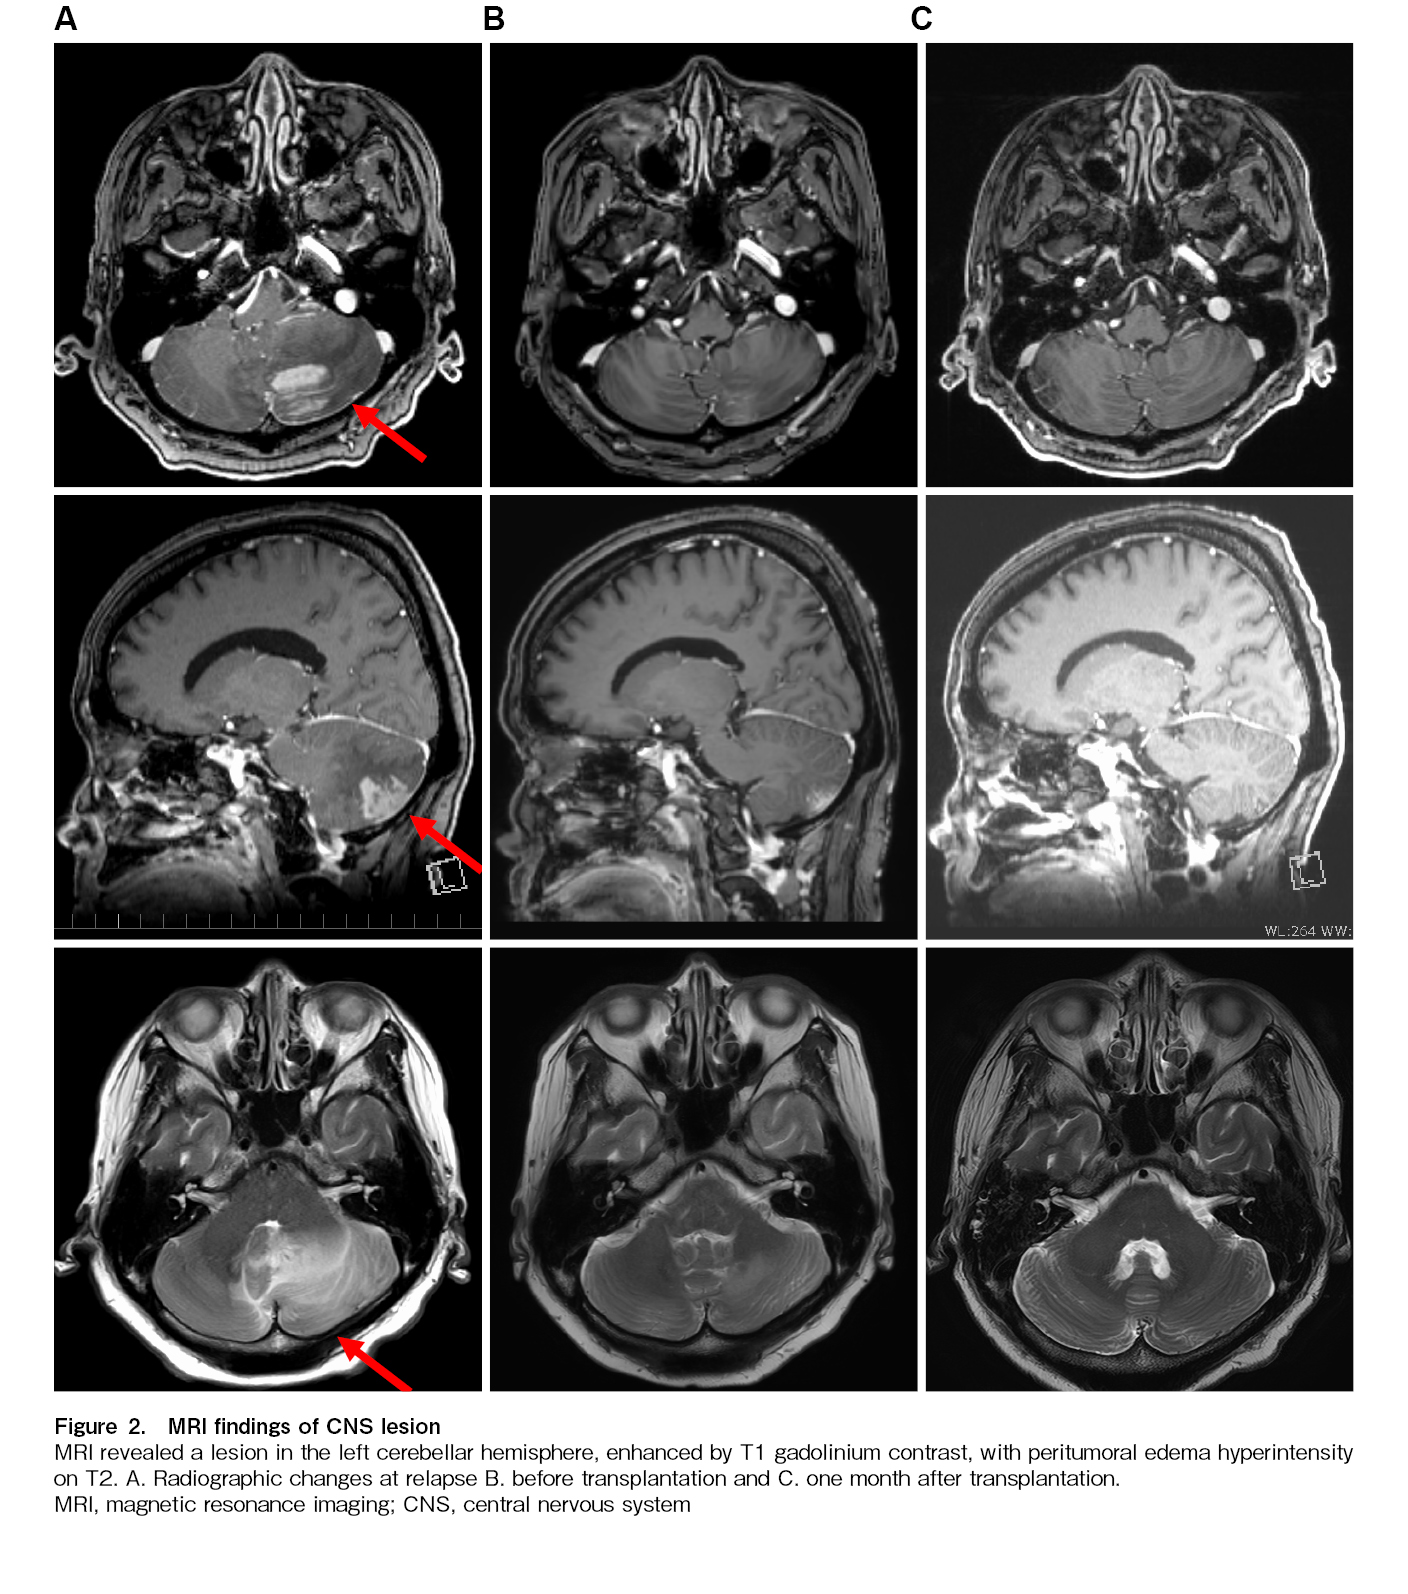

Twenty-two days after THP-COP second course initiation, at the time of hematologic recovery and in preparation for transplantation, the patient experienced systemic fatigue similar to that at initial presentation, accompanied by dizziness, gait unsteadiness, and horizontal nystagmus. Brain magnetic resonance imaging (MRI) subsequently demonstrated a gadolinium-enhancing lesion in the left cerebellar hemisphere (Figure 2A). EBV-DNA was detected (2.54 log IU/mL) and LDH level was elevated (139 U/L) on cerebrospinal fluid examination. Blood tests showed disease progression, with elevated EBV-DNA (4.22 log IU/mL) and LDH levels (682 U/L;

The reduced-intensity conditioning regimen was initiated on day 16 of DeVIC therapy, immediately after completion of whole-brain irradiation. We modified the conditioning regimen by adding high-dose cytarabine and administered haplo-SCT with PTCy (40 mg/kg for 2 days), following a reduced-intensity conditioning regimen (fludarabine, 30 mg/m2 for 6 days; busulfan, 3.2 mg/kg for 2 days; cytarabine, 2,000 mg/m2 for 2 days; and total body irradiation at 4 Gy) along with mycophenolate mofetil and tacrolimus. Peripheral stem cells collected from her younger brother contained 6.6×106/kg CD34-positive cells. Cyclosporine, which had been administered since the cooling therapy, was discontinued before the start of the conditioning regimen, and steroids were terminated 2 days before the SCT. No adverse CNS events occurred during conditioning. Oral mucositis and diarrhea appeared as regimen-related toxicities but were controlled via symptomatic treatment. Neutrophil engraftment was observed on day 16 post-transplant, and fluorescence in situ hybridization of the X/Y chromosome revealed complete donor chimerism. However, the patient continued to experience fever, erythematous papules, and diarrhea. Stage 1 gut graft-versus-host disease (GVHD) and stage 3 skin GVHD were diagnosed via lower gastrointestinal endoscopy and biopsy. Both were mildly relieved with topical steroids and non-specific treatments. Peripheral blood EBV-DNA remained undetectable 27 days after haplo-SCT, and MRI showed no residual disease (Figure 2C). Mycophenolate mofetil was administered until day 45. The patient was discharged on day 46 and achieved a complete metabolic response on day 103, as assessed using PET-CT. EBV DNA was detected in peripheral blood for approximately four months from day 107 but subsequently disappeared without intervention and was still not detected at one and a half years after transplantation. Tacrolimus tapering was initiated on day 75 and gradually accelerated thereafter, possibly allowing graft-versus-lymphoma effects to emerge and contributing to subsequent viral clearance. It was eventually discontinued on day 310.